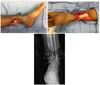

Which of the following conditions is a relative CONTRAINDICATION for use of the flap in the image shown for reconstruction of an 8 x 10-cm anterior ankle wound?

The correct response is Option D.

Diabetes mellitus can be associated with peripheral vascular disease, but by itself, would not prevent successful use of the reverse sural artery flap for foot or ankle reconstruction. Appropriate preoperative workup would include noninvasive ultrasound study of the lower extremity vasculature to prove the peroneal artery was patent.

The distally based sural artery flap receives its blood supply from a few sources, the most robust of which are perforators from the peroneal artery. The most distal of these perforators arise between 4 and 7 cm proximal to the lateral malleolus. Additional perfusion arises from neurocutaneous perforators from the sural nerve and venocutaneous perforators from the lesser saphenous vein.